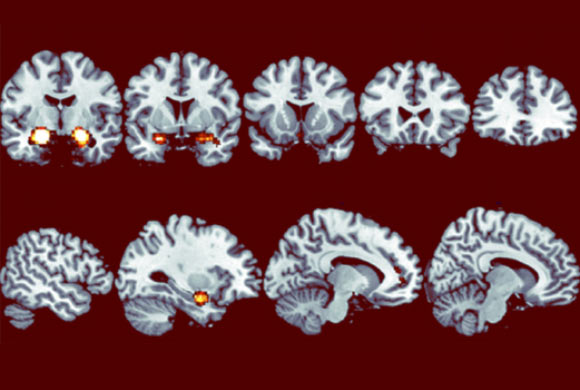

Giảm độ nhạy cảm với sự thiếu trung thực theo thời gian. Image credit: Neil Garrett và cộng sự.

Công trình nghiên cứu được báo cáo trên tạp chí Nature Neuroscience cảnh báo mọi người nên trung thành với sự thật vì nếu không, hậu quả sẽ ngày càng nghiêm trọng. Quá trình phân tích ảnh não ở nhóm tình nguyện viên từng cho thấy phản ứng cảm xúc mạnh mẽ trong tâm trí của họ khi nói dối lần đầu tiên trong một trò chơi phỏng đoán, nhưng tác dụng này giảm dần theo thời gian. Và, mặc dù người chơi ban đầu có xu hướng nói dối tương đối ít, họ dần trở nên không đáng tin, thể hiện qua hành động lừa gạt người chơi khác vì lợi ích riêng.

Qua thử nghiệm, các nhà khoa học phát hiện ra rằng, đầu tiên, người chơi sẵn sàng nói dối “chút chút”, nhưng điều này dần leo thang trong quá trình chơi. Hình ảnh não của nhóm đối tượng qua máy quét MRI cho thấy khu vực não liên quan đến cảm xúc, hạch hạnh nhân (amygdala) ban đầu phản ứng mạnh mẽ với lời nói dối, lại ngày càng “chai lì” theo thời gian. Sự suy giảm lớn trong phản ứng này cũng liên quan mật thiết đến những lời nói dối đặc biệt nghiêm trọng.

Cô Tali nhận xét: “Khi chúng ta nói dối vì lợi ích cá nhân, hạch hạnh nhân tạo ra cảm giác tiêu cực làm hạn chế mức độ lời nói dối. Tuy nhiên, phản ứng này mất dần khi chúng ta tiếp tục nói dối, dẫn đến quá trình “tuột dốc không phanh” của lòng trung thực kèm theo biểu cảm “xạo không chớp mắt”.